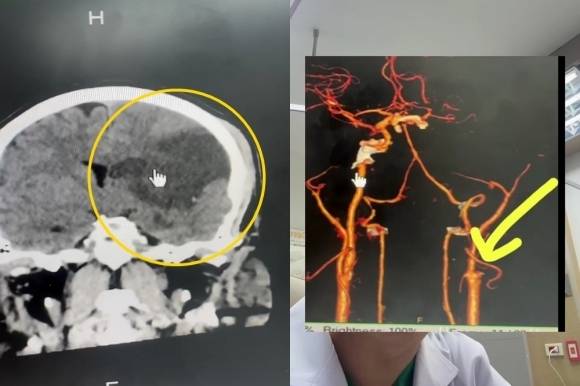

![경동맥이 끊어져 뇌 일부가 손상된 환자의 뇌 스캔(왼쪽) 결과. [SNS 갈무리]](https://img1.daumcdn.net/thumb/R658x0.q70/?fname=https://t1.daumcdn.net/news/202505/09/ned/20250509142038890czyg.jpg)

이 환자는 전날 저녁 식사를 마친 뒤 목이 뻐근해 아내에게 목 마사지를 부탁했다고 한다. 환자의 뇌를 스캔한 결과 왼쪽 뇌 상당 부분이 괴사한 것으로 확인됐다. 추가 검사 결과 경동맥이 끊어져 뇌로 들어가는 혈류가 막힌 것으로 나타났다.

컴퓨터 단층(CT) 촬영 결과 환자는 최소 8시간 이상 뇌의 혈액 순환이 제대로 이뤄지지 않은 것으로 추정됐다.